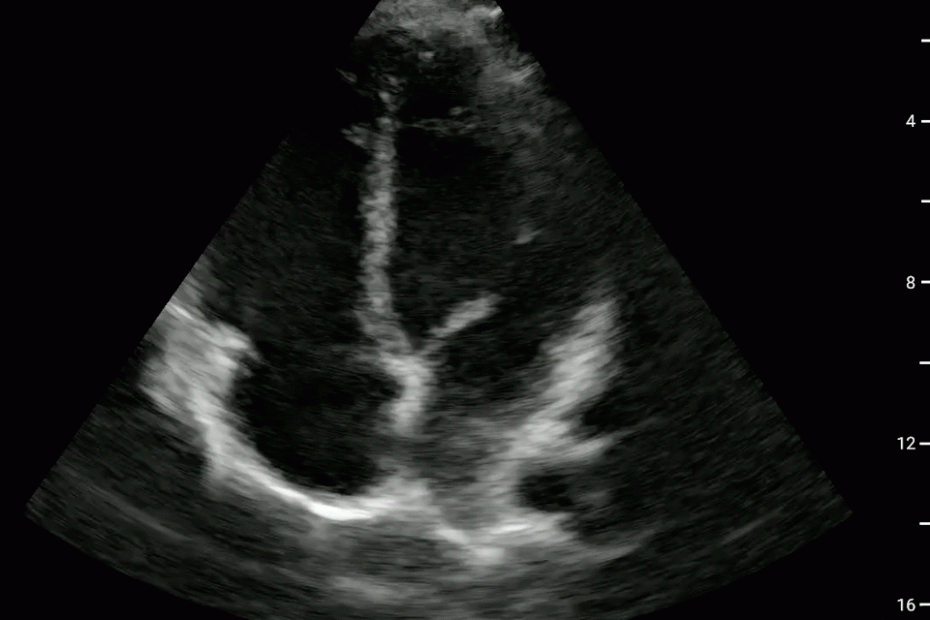

Pericardial and Pleural Effusions

Pericardial Effusion

Pacer Lead Migration

Mitral Valve Prolapse

Left Atrial Mass

Complete Heart Block

Atrial Flutter

Supine vs Left Lateral Decubitus

Normal 4 View Echo